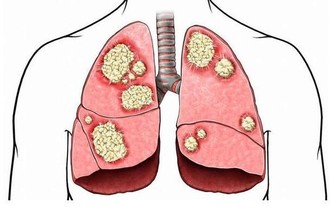

在我們人體里分布最廣的應該就是血管,血管遍布全身每個角落,正是血管的存在,才能夠保障身體各個臟器得到足夠的氧氣和營養,可是隨著年齡的增長,血管也會出現老化,血管的彈性也會逐年降低,而此時血管的收縮和擴張也會有所減退,所以隨之而來的就是各種各樣的血管問題,當然這是一種正常現象,雖然我們無法避免,但是我們卻可以通過一些人為的干預延緩他們的到來,接下來我們一塊來看一下。

現在的年輕人有太多人不在意他們,總感覺自己年輕什麼都不怕,在日常生活中,他們認為很正常的一些事情,正在漸漸的傷害著自己的血管。這就是為什麼近幾年越來越多的年輕人頻頻發生血管硬化等一系列的問題,影響機體正常的運作,緊接而來的就是各種各樣的血管問題。